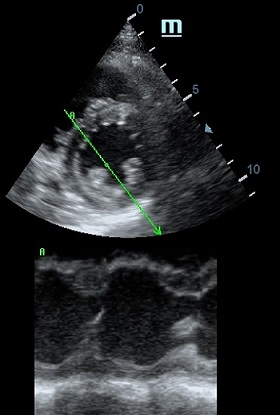

Но как же провести стандартные измерения в М-режиме, если мы его не использовали? На помощь приходит функция Free Xros M – анатомический М-режим. Имея записанную в память прибора видео петлю, мы можем провести линию М-режима в любом месте, при этом корректируя изначально не оптимальный угол.

Возможности применения функции многогранны: от измерения толщины стенок левого желудочка, движения створок митрального клапана и кооптации нижней полой вены до оценки сократимости миокарда как глобально, так и по сегментам.

Показатели УЗ сканирования в М-режиме

Какие показатели можно использовать при анатомическом М-режиме помимо привычных срезов через конец створок митрального клапана или синуса Вальсальве?